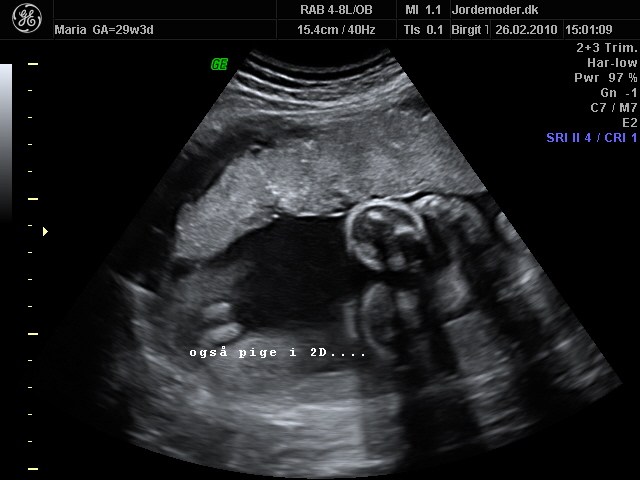

Først i 3D og så i 2 D..

Vedhæftede fotos (klik for at se i fuld størrelse)

Helt tydeligt, tak. En lille dreng . Synes også at det er meget nemmere på 3 D scanningerne. Du har ikke et fra 2 D vel?

Også helt tydeligt. Så tydelig er mit billede slet ikke selvom scanningsjordmoderen kunne se det efter 10 sek